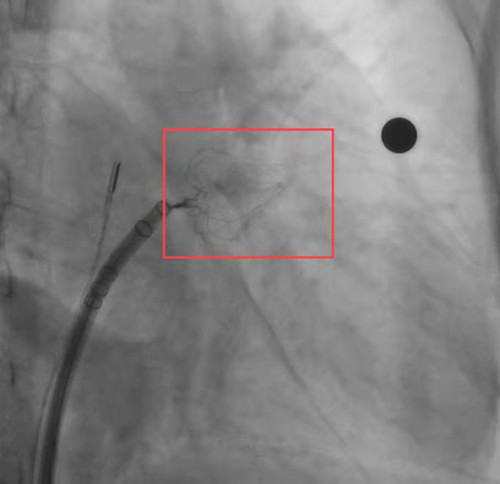

术前左心耳造影